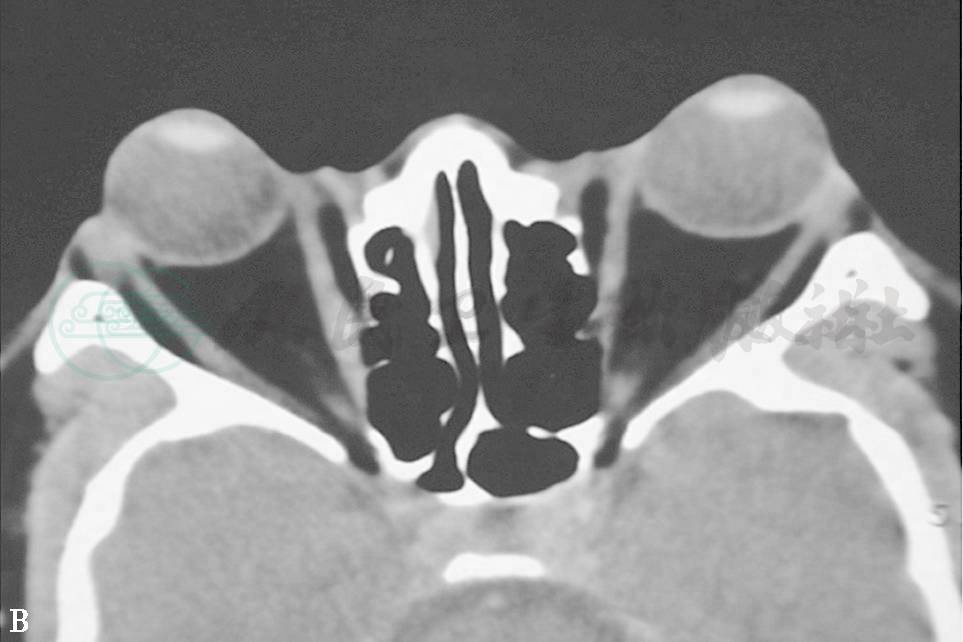

TAO常有限制性眼外肌病变,又称甲状腺眼外肌病,眼外肌轻度受累者临床不易确定,CT或MRI检查可显示出眼外肌长大。垂直肌受累比水平肌更易受累。下直肌受累最常见,占60%(图1A、B、C),依次为内直肌50%,上直肌40%(图2D、E)和外直肌29%。但眼外肌病变通常为双侧,多条眼外肌增大并不少见。CT扫描(轴位及冠状位)显示肌腹呈纺锤状扩大,边界清楚,肌腱不增大。TAO临床可根据患者复视,眼球运动受限,眼球移位,眼眶CT扫描证明眼外肌增大者占93%。TAO眼眶CT扫描时不能只作水平扫描,否则容易将单眼的下直肌增大误认为眶内肿瘤,作冠状扫描后方可得出正确诊断。

图1眼外肌病(下直肌)

A.左眼球呈下转位 B.眼眶CT冠状扫描见下直肌增大 C.右眼眼球呈上转位